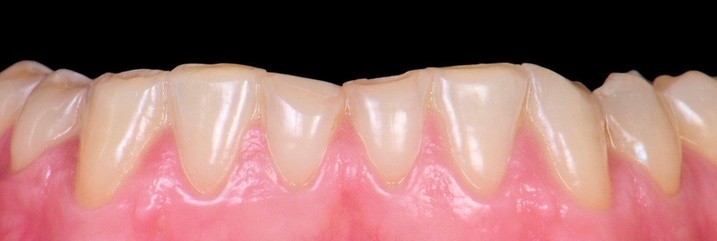

Тиунов Илья Игоревич: портфолио (19)

Имею международную сертификацию. Делаю лучшие виниры. Высокопрофессионально протезирую и реставрирую зубы. Работаю в комплексном подходе с командой специалистов: хирургом, терапевтом, гигиенистом и ортодонтом. Жизнь моя — публична. Работа — профессиональна. Намерения — серьезны. Ответственность — высока. Слог — краток.